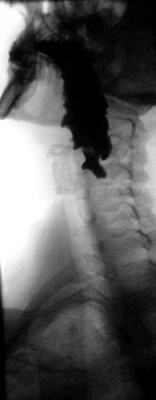

Дивертикул пищевода — это ограниченное выпячивание слизистой оболочки через дефект в мышечной оболочке стенки пищевода.

Главным методом в диагностике дивертикулов является полипозиционное рентгенконтрастное исследование, которое позволяет выявить локализацию, форму, размеры дивертикула. В роли контраста используют бариевую смесь. Также обязательно эзофагоскопическое исследование позволяющее выявить изменения слизистой, а также наличие различных осложнений (кровотечение, полип, рак).